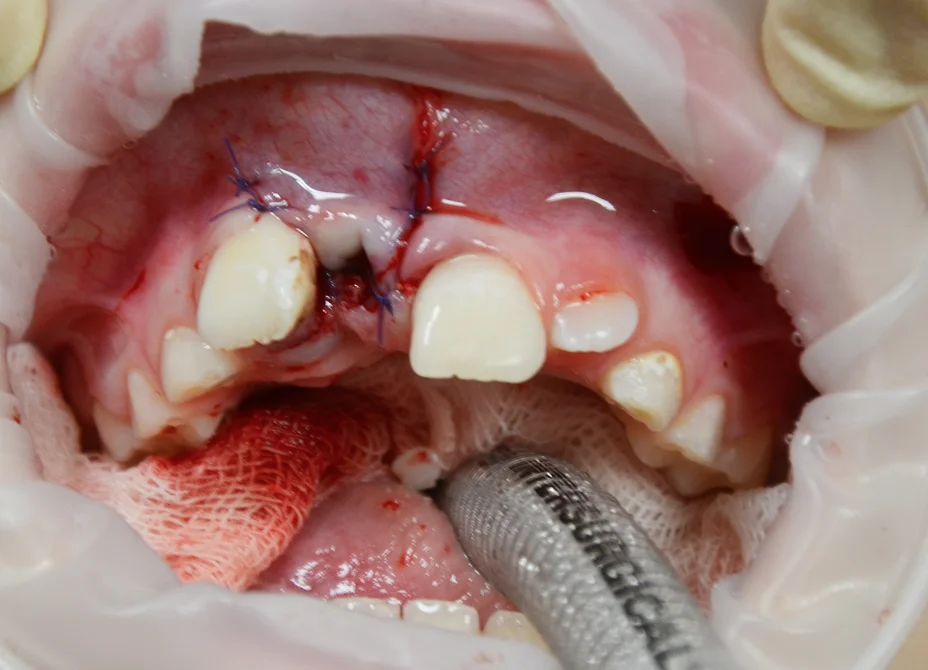

Олигодентия, адентия, сверхкомплектные зубы: диагностика и план лечения.

Основные состояния, сопровождающиеся нарушением числа зубов. Наиболее частые локализации сверхкомплектных зубов. Последствия олигодентии и сверхкомплектных зубов.

Зуб в зубе (dens invaginatus): диагностика и тактика лечения

Механизм формирования инвагинации. Клинические проявления и рентгенологическая картина. Риски осложнений и алгоритм принятия решения о лечении. Особенности эндодонтического лечения при разных степенях инвагинации.